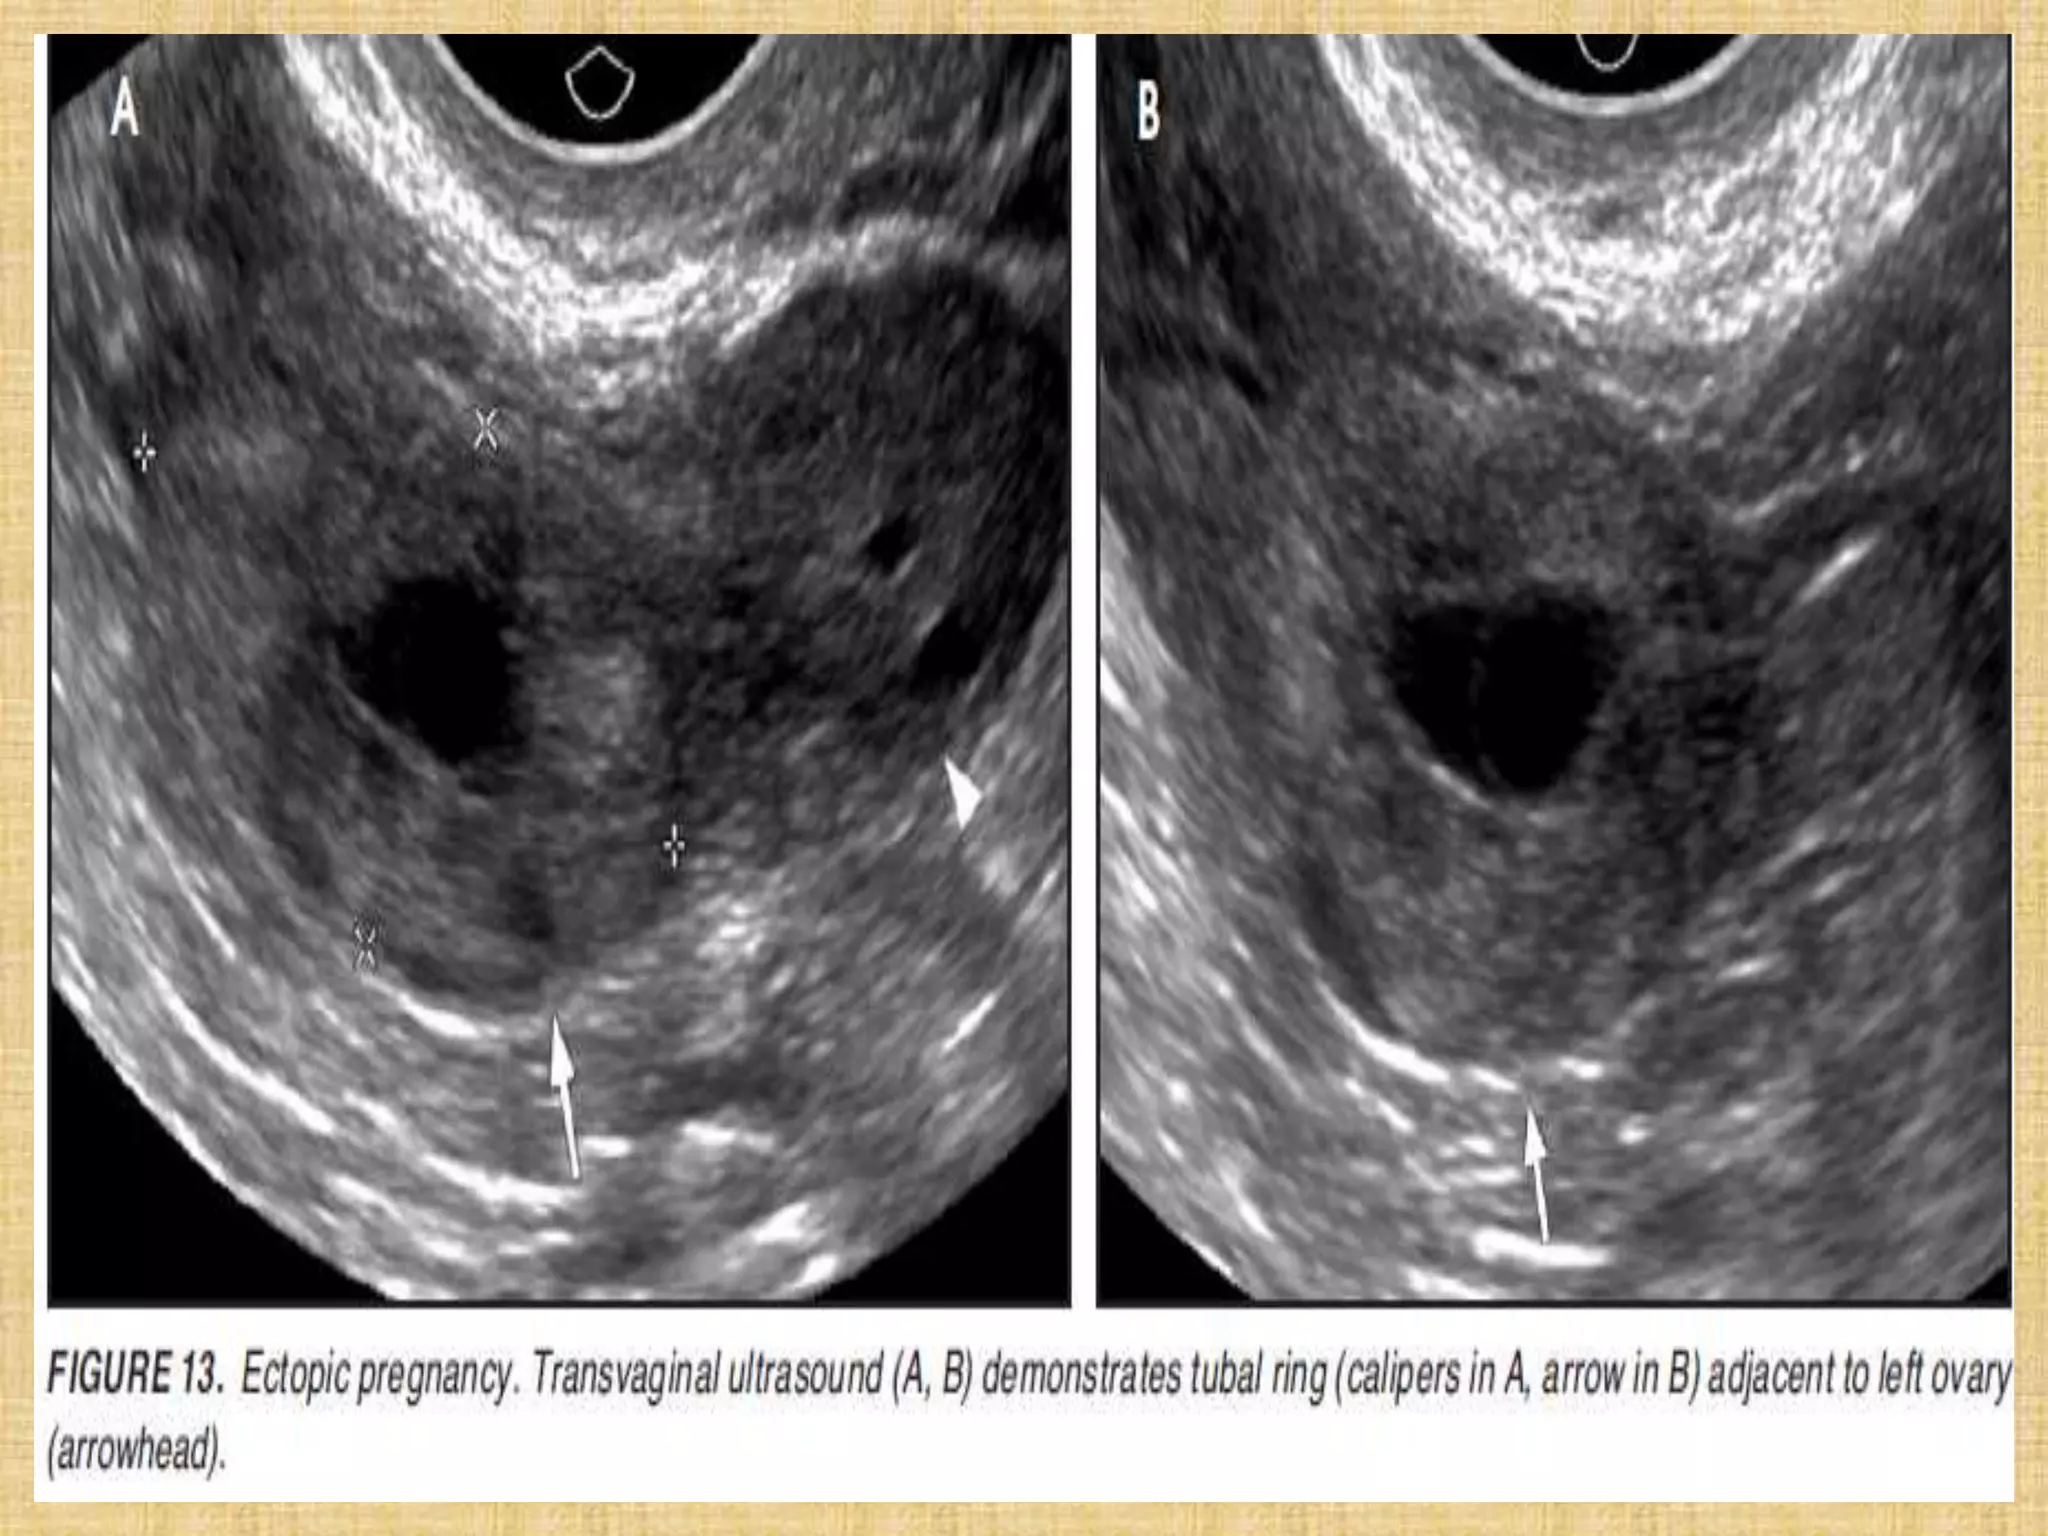

Tubal ring of ectopic pregnancy. (a) Transvaginal transverse view of the left adnexa shows

an echogenic ringlike mass (arrows) medial to the left ovary. Within the left ovary is a

thick-walled corpus luteum cyst (arrowheads). Note that the wall of the ectopic pregnancy

is more echogenic than the wall of the corpus luteum cyst. (b) Color Doppler image shows

more blood flow (arrowheads) to the corpus luteum than to the ectopic pregnancy (arrow).

Note that the “ring of fire” (hypervascular ring) appearance in the adnexa can be seen with

both ectopic pregnancy and corpus luteum.

Tubal ring ofectopic pregnancy. (a) Transvaginal transverse view of the left adnexa shows an echogenic ringlike mass (arrows) medial to the left ovary. Within the left ovary is a thick-walled corpus luteum cyst (arrowheads). Note that the wall of the ectopic pregnancy is more echogenic than the wall of the corpus luteum cyst. (b) Color Doppler image shows more blood flow (arrowheads) to the corpus luteum than to the ectopic pregnancy (arrow). Note that the “ring of fire” (hypervascular ring) appearance in the adnexa can be seen with both ectopic pregnancy and corpus luteum.